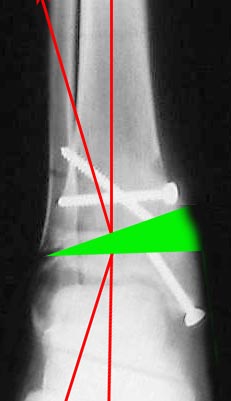

Согласен, тут деформация меньше, но все-таки заметная, почти 20 градусов. Я бы устранял ее как на приложенной картинке.

При таком варианте с аппаратом все легко и просто. С пластиной - должны быть трудности. Может быть, следовало бы планировать коррекцию как-то иначе? Как?